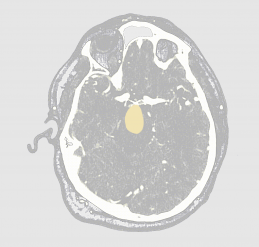

[ stories on progress ] making headlines | Medical AI software detects aneurysms